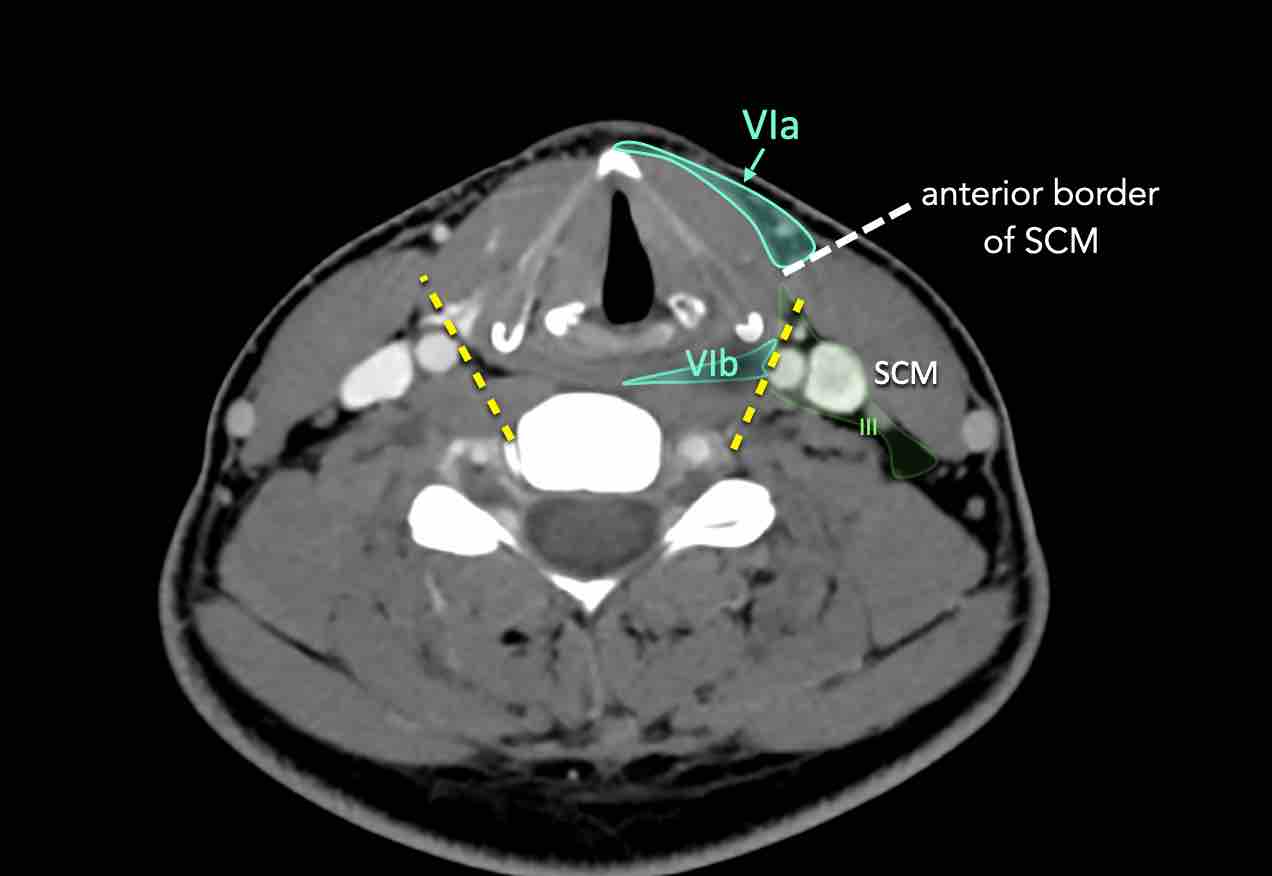

VI – Cổ trước

Tầng này chứa các hạch tĩnh mạch cảnh trước nông (tầng VIa) và các hạch sâu hơn bao gồm hạch trước thanh quản, trước khí quản, cạnh khí quản và hạch thần kinh thanh quản quặt ngược (tầng VIb).